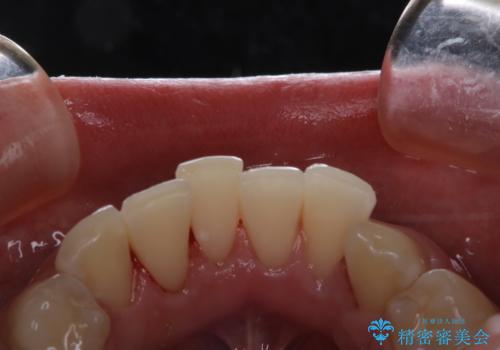

コーヒーの着色落としをPMTCでキレイに

- コーヒが好きで、ステインが付くことが気になるとのことで来院されました。PMTC30分コースを行いました。

PMTCでは、歯のトリートメントも行います。

毎日の歯磨きや飲食などにより、歯の表面に細かい傷がついてしまうため、その傷にステインや汚れなどが付着してしまいます。